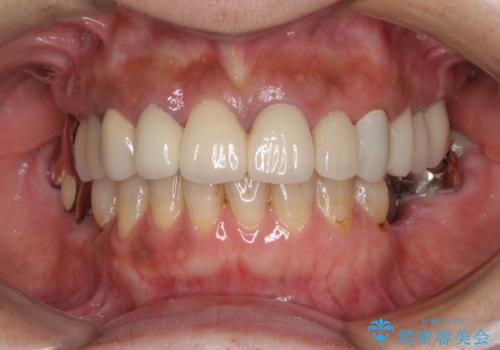

長い間億劫で手を付けていなかったものの、仮歯にした時点から自然な口元となり、視線が気にならなくなったとのことでした。

出来上がってきたセラミッククラウンはまるで自身の歯のようで、患者様には大変満足していただきました。